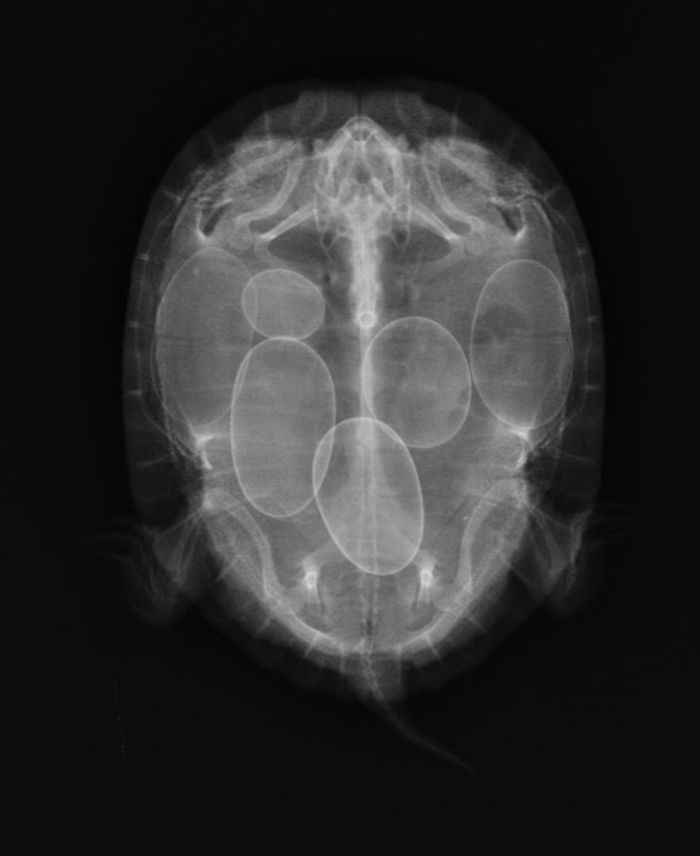

X-Ray Of A Turtle With Eggs

X-Rayed A Turtle